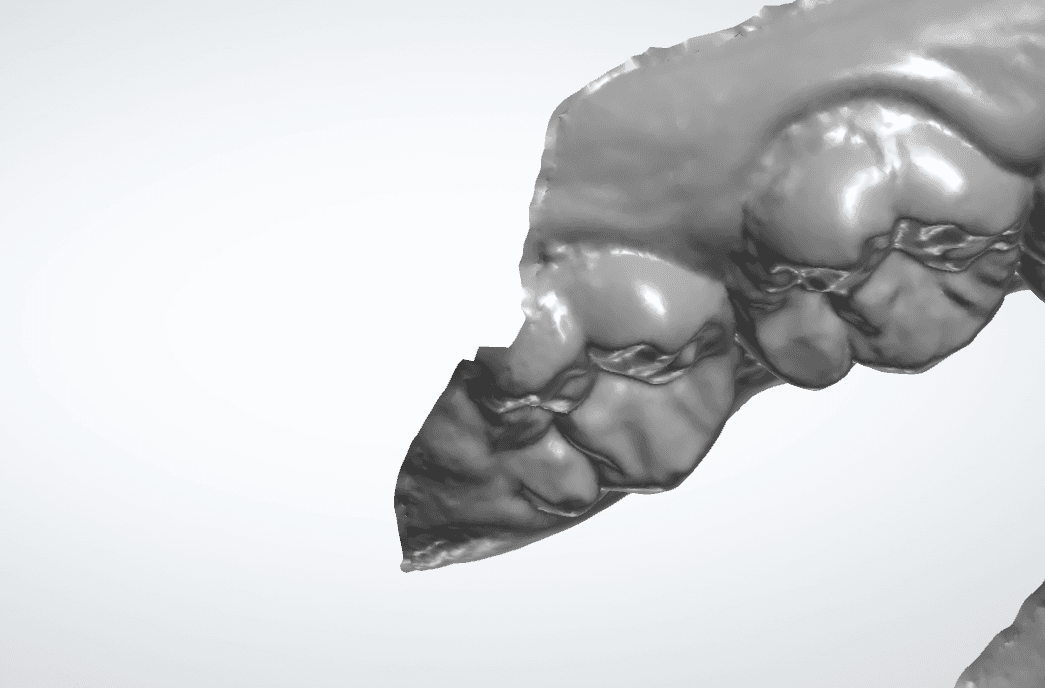

Distal do segundo molar superior

Essa região é muito comum de apresentar uma dificuldade para conseguir uma copia exata. Isso acontece por conta da falta de espaço para chegar com a cabeça do escaner nessa região.

Porém, a cópia completa da anatomia desse elemento, faz muita diferença em correção antero-posteriores aonde precisamos movimentar os molares. Muitas vezes precisamos pedir para o dentista/clínica de exame repetir o escaneamento.